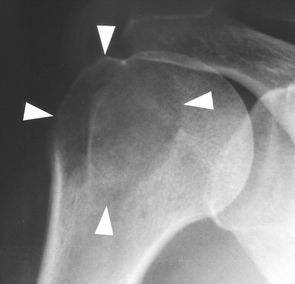

软骨母细胞瘤,通常存在于长骨的骨骺(或隆起)(图2A)。它们往往很小(<4 cm),大多数(≈75%)表现出硬化边界[2,3]。在三分之一的患者的X光片上可见钙化基质[4]。当软骨母细胞瘤延伸到干骺端并且缺乏硬化边缘和钙化时,它们可以模仿巨细胞瘤(图2B)。与巨细胞瘤不同,软骨母细胞瘤存在于较年轻的年龄组,通常在骨骼成熟之前。软骨母细胞瘤很少将肿瘤扩展到软组织中。

图2A-软骨母细胞瘤。16岁女孩的射线片显示典型的肱骨近端骨骺的软骨母细胞瘤(箭头)。

图2B-软骨母细胞瘤。16岁男孩胫骨近端干骺端和骨骺(箭头)有非硬化边缘, X线外观很像巨细胞瘤,但是由于年龄较小,不能明确诊断为典型的骨巨细胞瘤。